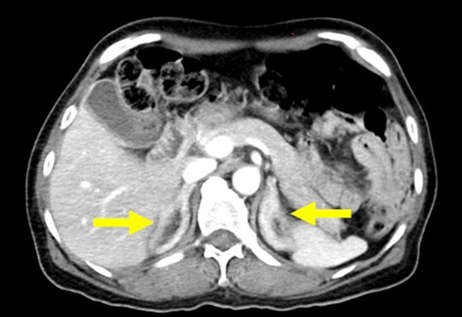

The initial brain computerized tomography (CT) scan showed no acute intracranial anomalies. Fluid-attenuated inversion recovery (FLAIR) imaging on magnetic resonance imaging (MRI) revealed bilateral multifocal high-intensity lesions in both cerebral hemispheres, along with high-intensity lesions in the brainstem and cerebellum (Figure 1). These findings, combined with neurological manifestations and severe hypertension, though atypical, raise the possibility of posterior reversible encephalopathy syndrome (PRES). Based on the laboratory results, abdomen and pelvis computed tomography (CT) scans were performed to investigate potential causes of secondary hypertension and adrenal gland abnormalities. The CT scan revealed diffuse bilateral adrenal glands enlargement (Figure 2). Furthermore, renal duplex ultrasound showed a normal hemodynamic pattern without evidence of renal artery stenosis.

Figure 2: A reprehensive transverse abdomen-pelvic computed tomography (CT) scan image showing bilateral adrenal glands hyperplasia (yellow arrows).